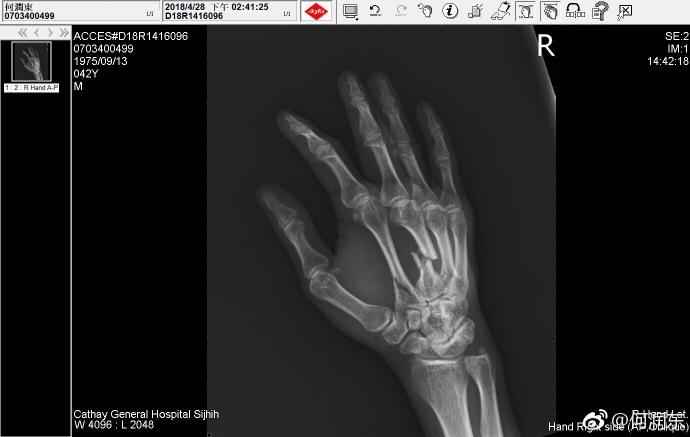

不知道他是在拍戏中受的伤,还是健身中。细看X光拍摄的时间,何润东这次受伤是在4月28日。五一劳动节的时候他还用裹着绷带的手给劳动者致敬,裹这么厚,当时就应该想到他伤得重才是。